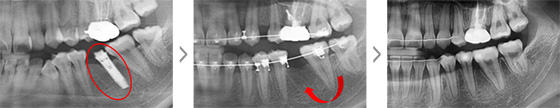

2년 전 식립한 임플란트의 보철물이 탈락된 상태로 1년간 지내오신 25세 여성입니다. 임플란트 식립을 위해 사용한 인공 뿌리를 제거하고 치아가 가지런해 지길 원하셨습니다. 자연치아로만 치료를 진행할 수 있도록 하기 위해 인공 뿌리를 제거하고, 빈 공간으로 치아를 이동시켰습니다.

① Trephine Drill과 bur를 이용하여 임플란트 fixture 제거

② 결손 부위의 치조골 내로 후방 어금니들의 뿌리가 위치되도록 이동 및 조절

임플란트 제거 후 생긴 빈 공간으로 브라켓을 부착한 사랑니를 이동시켜 추가적인 임플란트 식립이나 보철 치료 없이도 자연스러운 치열을 갖게 되었습니다.